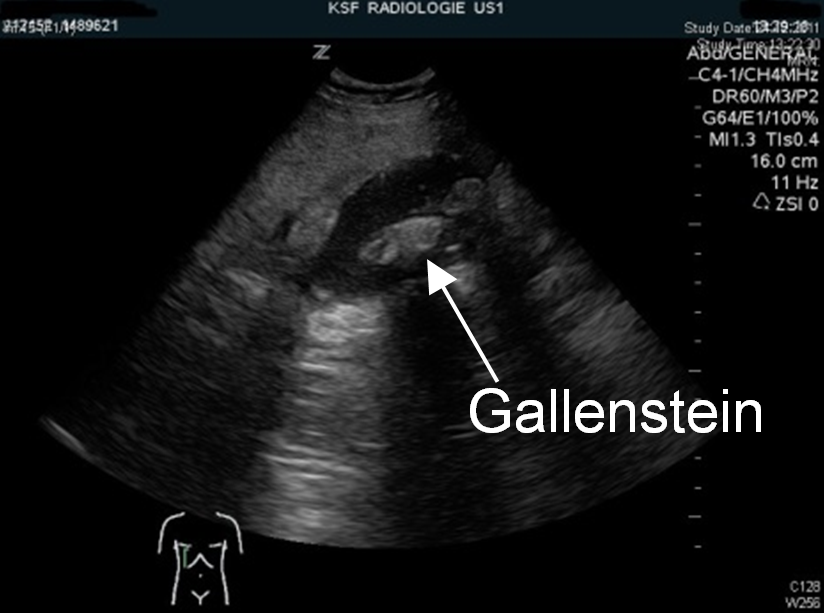

• Sonographie: Diese dient dem Nachweis von Gallensteinen, Entzündungen der Gallenblase, Gallengangsteinen oder anderen Ursachen der Beschwerden. Bezüglich der Gallenblasenentzündung ist dies die Diagnostik der Wahl.